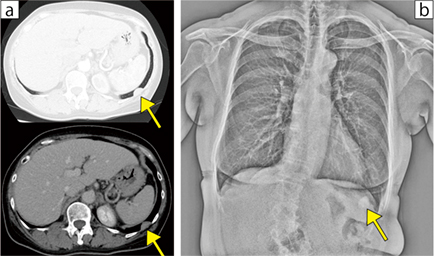

X線動態撮影が疾患の鑑別に役立った症例を提示する。症例3は,8年前に胸部異常陰影を指摘され,胸壁腫瘍疑いで経過観察を行っていたが,徐々に増大傾向のため手術の方針となった。術前の胸部単純撮影では腫瘍を指摘できず,CT(図3 a)で左第10肋間に胸腔内に凸な形状を示す22mm大の病変(↑)が認められ,胸壁腫瘍が考えられた。一方,X線動態撮影のFE-MODE(図3 b)では,腫瘍と思われる結節影(↑)が呼吸運動で肺とともに移動する様子が観察された。この所見から臓側胸膜疾患の可能性が高いと考えられたため,総合的に検討し,肺切除の手術アプローチにて手術を開始した。手術所見にて左肺S10に胸膜変化を伴う腫瘍が確認され,胸腔鏡下で肺部分切除を行い,病理検査にて良性の孤立性線維性腫瘍(SFT)と診断された。

図3 症例3:疾患の鑑別に役立った症例